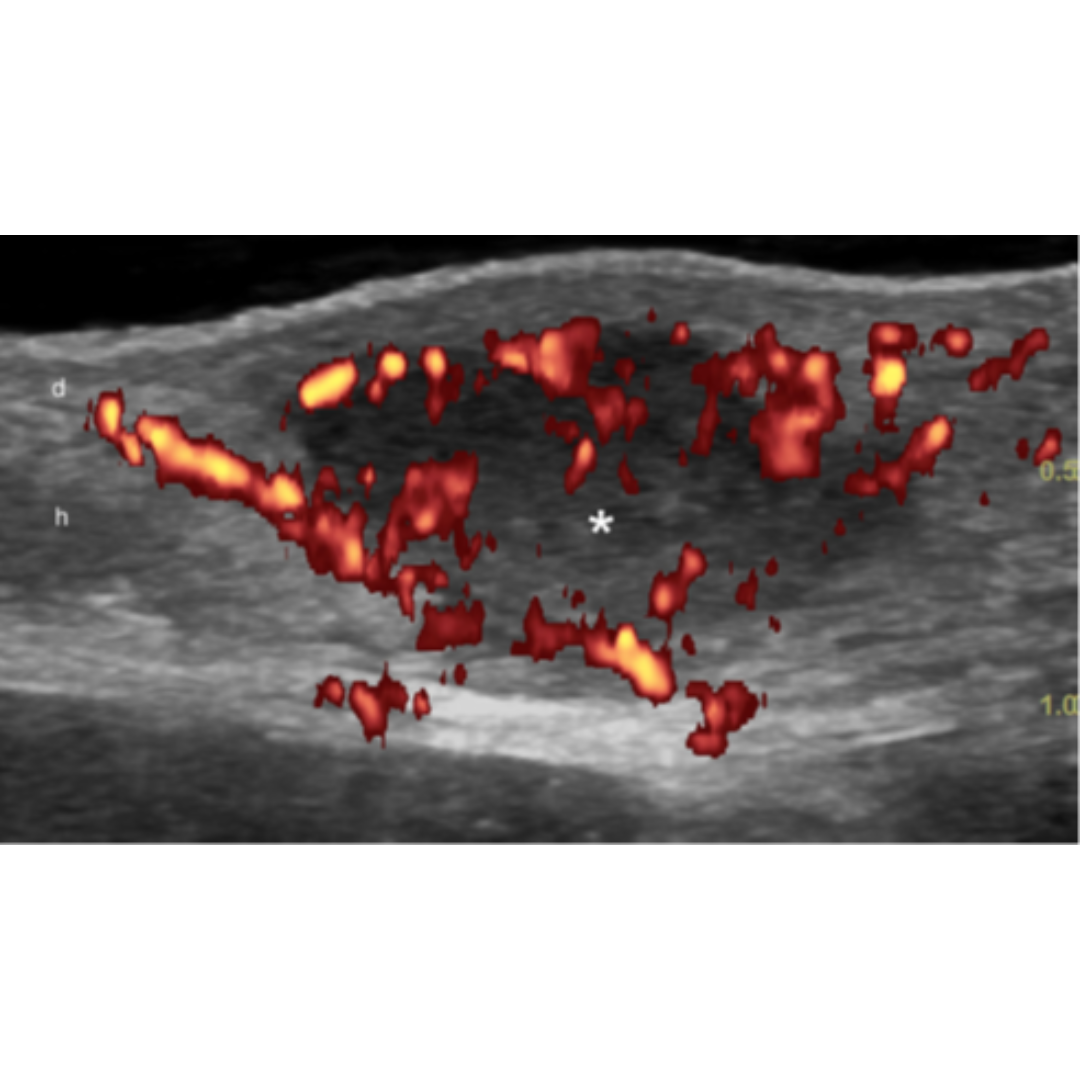

Existe además del estadio la clasificación del trayecto fistuloso descrito en la tabla 3, esta clasificación se basa en el Grado de fibrosis y edema de los trayectos fistulosos. Ecográficamente los grados de fibrosis se observan como halos rodeando las fistulas (figura 8) y el edema se observa rodeando los trayectos fistulosos como áreas hipoecogénicas en la hipodermis ejemplificados en figura 7. El grado de edema también se relaciona con la presencia de vascularización interna de la fistulas (figura 6).

Figura 5: Hidradenitis supurativa con una inflamación activa. La señal a Power Doppler demuestra un aumento del flujo sanguíneo de la lesión y en la periferia.